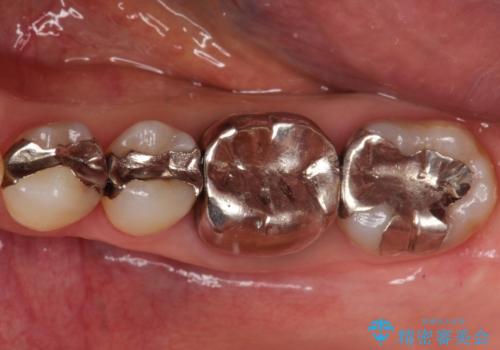

【メタルフリー】白い歯を手に入れたい

- 40代女性

- 2ヶ月

- 金属を外して白い歯を手に入れたいとのことで来院されました。

まとめて治療することで通院回数を減らすことができ、見た目も大変満足していただきました。